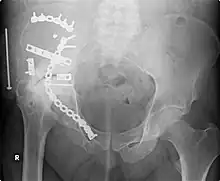

![]() This fracture of the lower cervical vertebrae is one of the conditions treated by orthopedic surgeons and neurosurgeons. | |